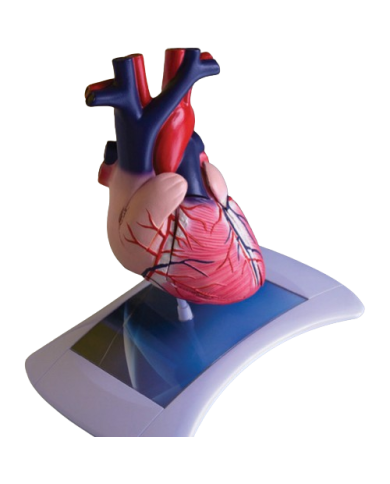

Modello anatomico PER FORNITURE CASE FARMACEUTICHE

Modello anatomico PER FORNITURE CASE FARMACEUTICHE

Modello anatomico PER FORNITURE CASE FARMACEUTICHE

Modello anatomico PER FORNITURE CASE FARMACEUTICHE

Modello anatomico PER FORNITURE CASE FARMACEUTICHE

Modello anatomico PER FORNITURE CASE FARMACEUTICHE

Modello anatomico PER FORNITURE CASE FARMACEUTICHE

Modello anatomico PER FORNITURE CASE FARMACEUTICHE

Modello anatomico PER FORNITURE CASE FARMACEUTICHE

Modello anatomico PER FORNITURE CASE FARMACEUTICHE

Modello anatomico PER FORNITURE CASE FARMACEUTICHE

Modello anatomico PER FORNITURE CASE FARMACEUTICHE

Modello anatomico PER FORNITURE CASE FARMACEUTICHE

Modello anatomico PER FORNITURE CASE FARMACEUTICHE

Modello anatomico PER FORNITURE CASE FARMACEUTICHE

Modello anatomico PER FORNITURE CASE FARMACEUTICHE

Modello anatomico PER FORNITURE CASE FARMACEUTICHE

Modello anatomico PER FORNITURE CASE FARMACEUTICHE

Modello anatomico PER FORNITURE CASE FARMACEUTICHE

Modello anatomico PER FORNITURE CASE FARMACEUTICHE

Modello anatomico PER FORNITURE CASE FARMACEUTICHE

Modello anatomico PER FORNITURE CASE FARMACEUTICHE